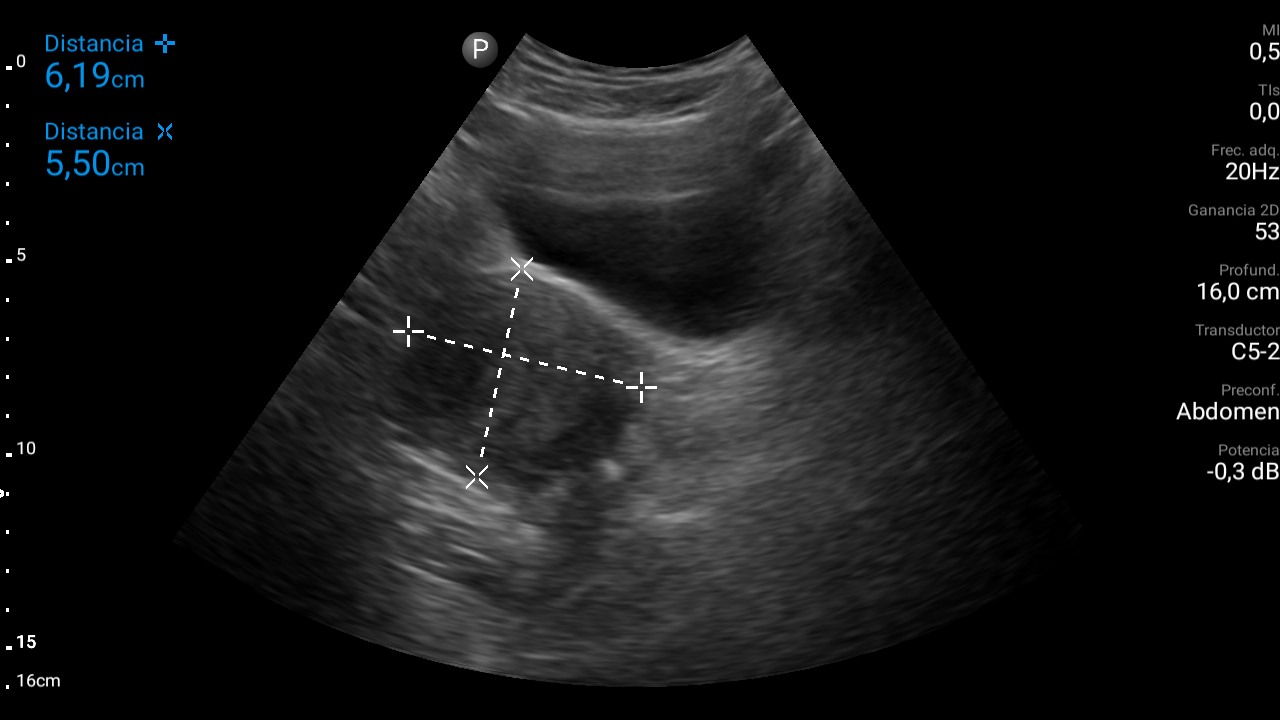

Ecografía abdominal: se observa masa hipoecoica dependiente de útero por lo que se remite de forma preferente a ginecología.

• Ecografía transvaginal: masa uterina compatible con mioma uterino.

Diagnóstico: mioma uterino.